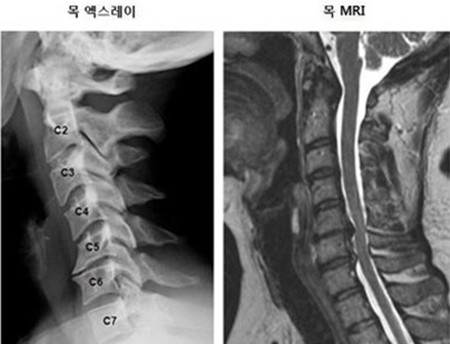

목 뼈와 뼈 사이의 디스크가 제자리에서 이탈되어 신경을 압박하던가 뼈 조직이 비정상적으로 자라 목을 지나는 척추 신경이 눌려 통증을 인지하는 질환이고요.

드문 드문하게 가슴 쪽에 통증이 일어날수 있고요. 목에서 가슴으로 걸치는 신경이 압박되어 통증이 일어나기 때문인데 하지만 가슴통증은 다른 원인을 통하여도 출현하는 된다면가 많으니 정확히 간파하려면 X-ray를 찍어서 확인하는 것이 좋을겁니다.

목 디스크 증상은 어깨, 목 손목등 근육에 통증을 기인하여 인지를 할 수 있다고 합니다. 목디스크 증상 초기에는 하루종일 근육이 뻐근하였거나 찌릿찌릿한 통증이 동반된다고 합니다. 만에 하나라도 경추 가운데 통증을 느끼시는 분들 중에는 지나친 경우 하반신 마비까지 올 수 있기 때문에 조기치료가 필수입니다.